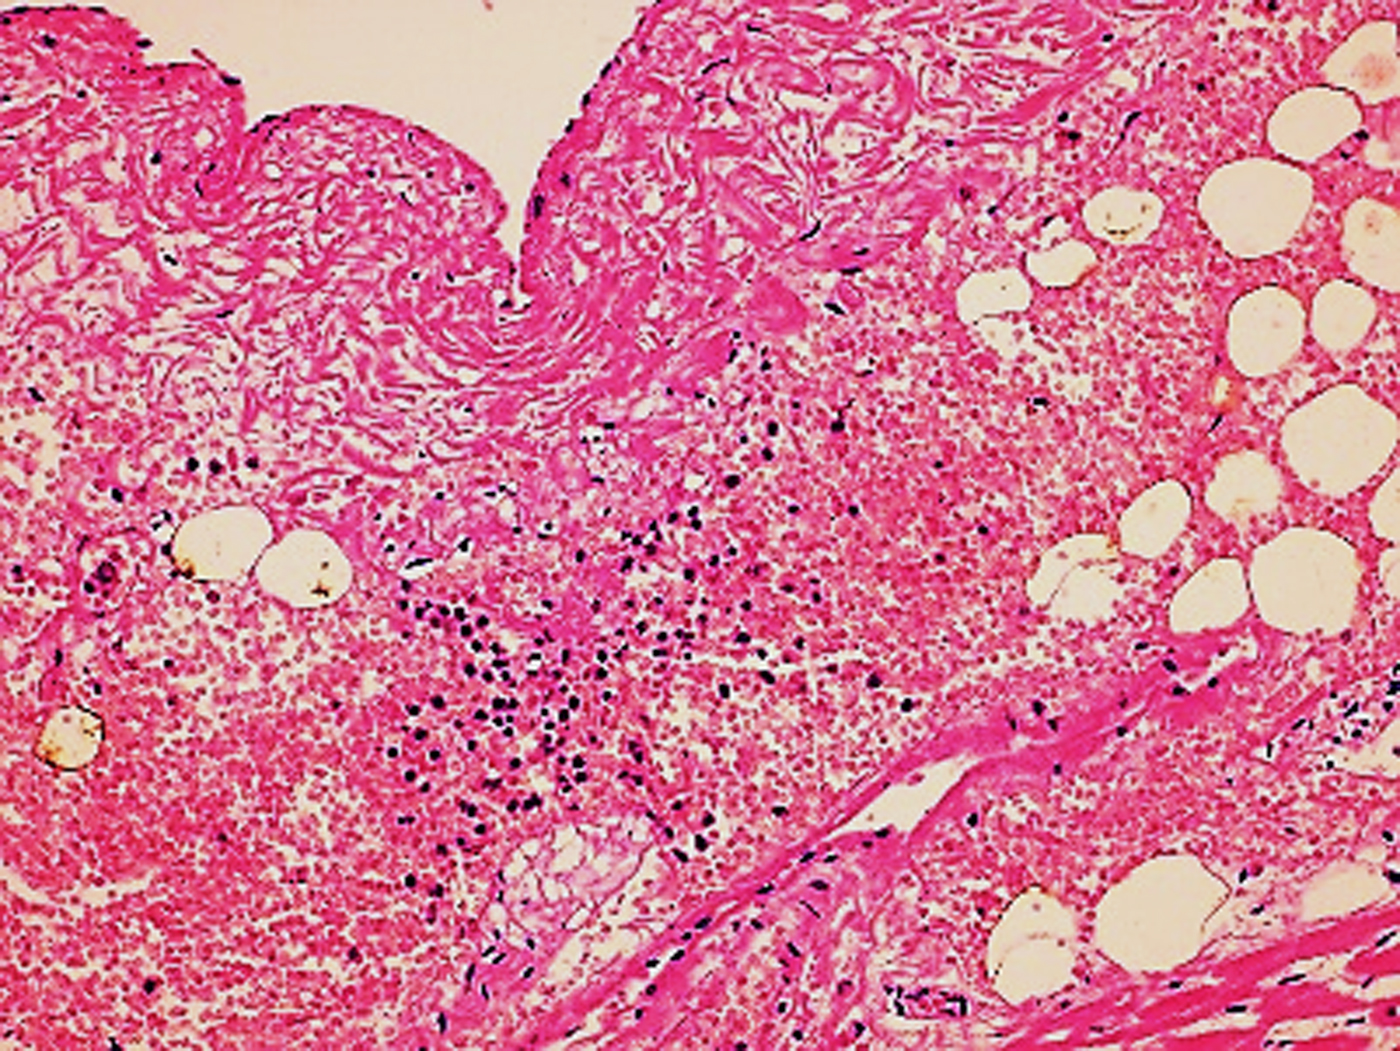

The autopsy revealed petechiae and generalised oedema (Fig. 1), congestion and focal haemorrhage in multiple organs associated with generalised vasculopathy of small-medium vessels with partial fibrin microthrombi formation, pericardial, pleural and peritoneal effusion, and interstitial pneumonitis with diffuse alveolar damage (Fig. 2). Additionally, the patient had foci of endo-myocarditis, acute renal tubular necrosis and chronic hepatitis.

Fig. 2. Interstitial pneumonitis and diffuse alveolar damage (HE 100×).